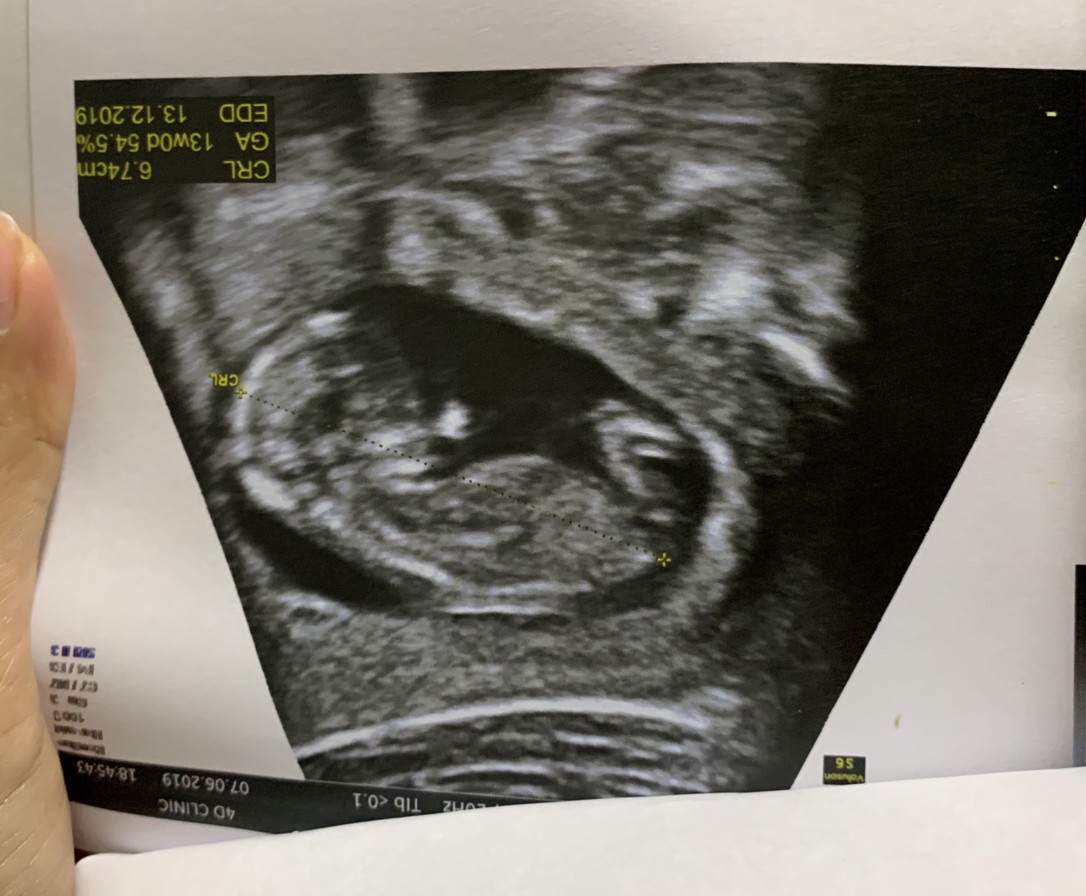

แม่บ้านนี้อยากได้ลูกสาวค่ะ #กำหนดคลอด 12 ธันวาคม #รูปซาวด์ตอน 12W